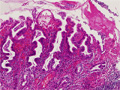

- ★(4)Gastritis (acute gastritis)

Gross appearance: Endoscopic view of AGML (acute gastric mucosal lesion). There is erosive gastritis demonstrated by multiple erosive, hemorrhagic foci in the gastric pylorus (arrow).